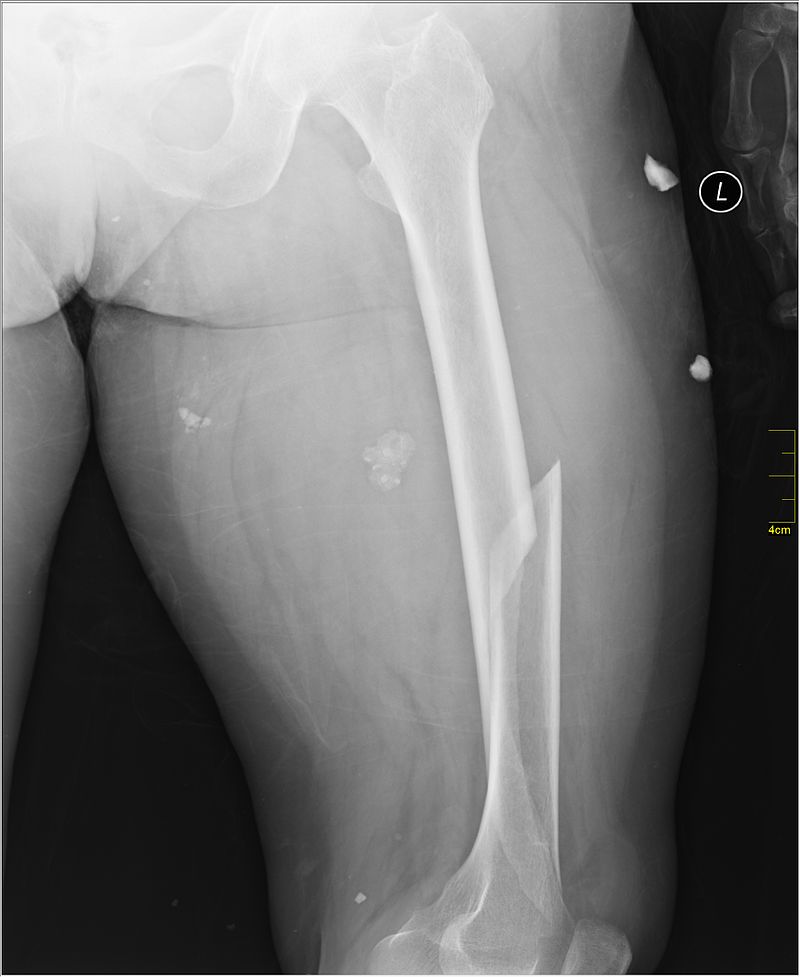

Anatomy of the femur including the long bone shaft

A femur fracture is a break in the thigh bone, or femur.

An x-ray or CT scan will help confirm the fracture.

The fracture can be a simple crack or severe enough to break the femur into pieces that can separate or even pierce through the skin.